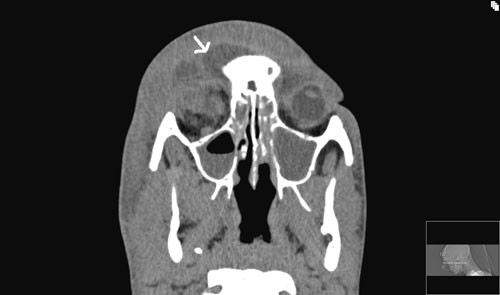

To dager etter andre operasjon hadde pasienten økende retrobulbære smerter over høyre øye. Ny CT-undersøkelse med kontrast viste økning av abscess bak bulbus occuli, mellom nervus opticus og musculus rectus medialis (fig 3).